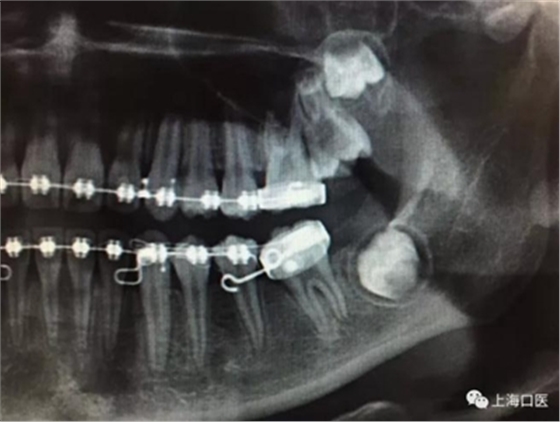

這是上海武廣增正畸工作室接診的一例非常規(guī)拔牙矯治病例,患者女性,初診年齡14歲。LL6殘冠拔除。LL7近中平移取代LL6,我們上傳了該患者一組下頜磨牙近中平移連續(xù)矯治過程的正畸X線片,與正畸界朋友分享。